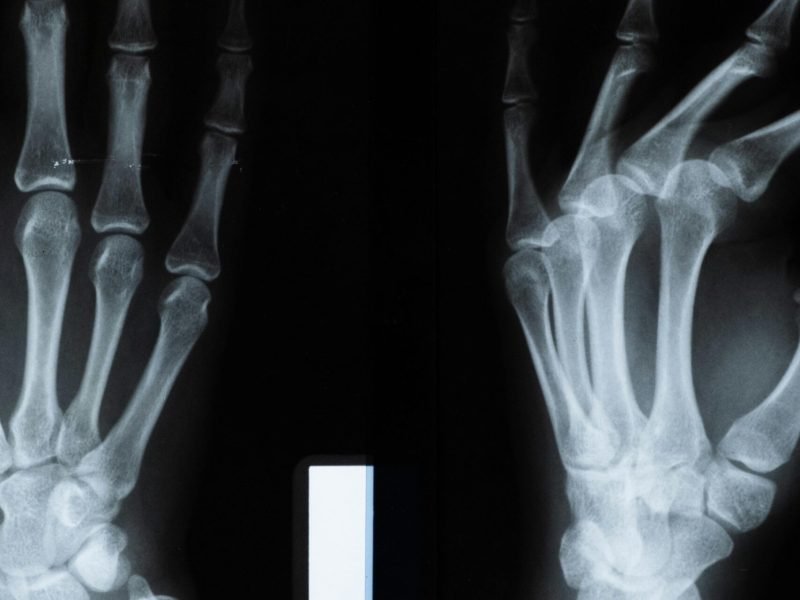

We offer specialized hand and foot surgeries to treat injuries, deformities, and chronic conditions, using precise techniques to restore full function and mobility.